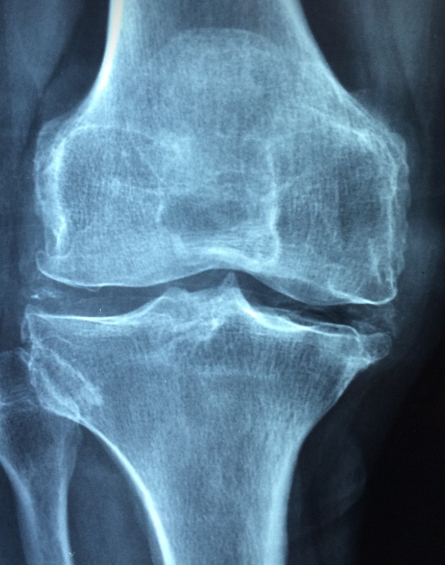

골다공증 원인부터 고관절 위험까지, 당신이 꼭 알아야 할 모든 것혹시 뼈 건강을 소홀히 하고 계신가요? "생로병사의 비밀" TV프로그램에서 골다공증에 대해 나왔습니다. 골다공증은 조용히 진행되지만 한순간의 골절로 큰 문제가 될 수 있습니다. 골다공증은 증상이 거의 없지만, 한 번 골절이 발생하면 회복이 어려운 무서운 질환입니다. 건강한 미래를 위해 지금부터 골다공증에 신경 써야겠습니다.목차1. 골다공증의 주요 원인 2. 골다공증의 증상과 조기 발견 3. 골다공증 예방을 위한 생활 습관 4. 골다공증 치료 방법 5. 고관절 골절과 골다공증의 관계 6. 뼈 건강을 위한 영양과 식단골다공증의 주요 원인 골다공증은 여러 가지 원인으로 발생하지만, 가장 중요한 요인은 나이와 호르몬 변화입니다. 특히 폐경 이후 여..